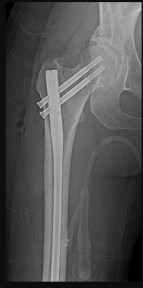

Figures 12a and 12b are a recent radiograph and a whole-body bone scan of an 81-year-old man who has hip pain and difficulty walking. His medical history is significant for obesity, hypertension, chronic kidney disease, and coronary artery disease. An examination demonstrates

moderate tenderness with passive range of motion of the left hip and an inability to actively flex the left hip against gravity. What is the best next step?

This patient has no known history of active malignancy. The radiograph shows a lesser trochanteric avulsion fracture (a fracture routinely associated with an underlying neoplasm). The bone scan reveals no other bone lesions. The femur fracture is statistically most likely to occur because of metastatic disease, but, without other evidence of metastasis, a primary bone sarcoma is possible, and biopsy is recommended before surgical fixation. Observation of this fracture, which is pathognomonic for neoplastic disease, is strongly discouraged.